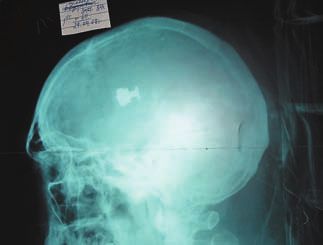

Ранение представляло собой слепое диаметральное проникающее повреждение правой височно-теменной области головного мозга с дырчатым переломом правой теменной кости (ил. 1). При рентгенологическом обследовании и компьютерной томографии черепа в левой височной доле была обнаружена пуля (ил. 2, 3).

Ил. 2. Рентгенограмма черепа, боковой снимок. Видна тень пули патрона18х45Т